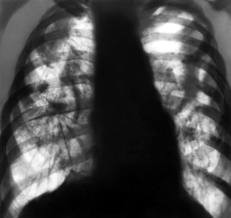

Эмфизема легких

Эмфизема – это процесс, при котором в легких происходит снижение подвижности тканей, повышается воздушность. Довольно часто поражаются все легкие, но иногда пораженные участки сочетаются и с участками нормальной ткани легких. Такая экзема называется буллезной.

Причинами возникновения заболевания является хронический запущенный бронхит, причинами образования буллем – наследственные факторы, тяжелые перенесенные болезни. Читать далее